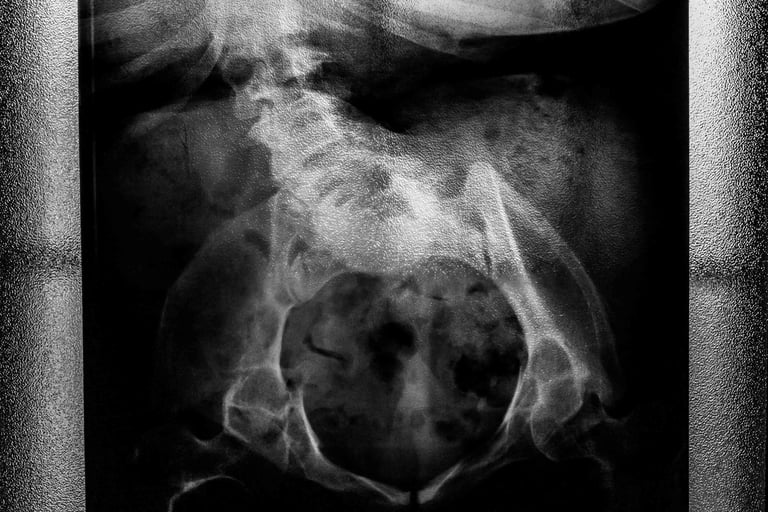

Carla, la protagonista, è una donna affetta da spina bifida, incontrata inizialmente come possibile soggetto per raccontare la disabilità. Quello che all’inizio appare come un progetto legato a una condizione fisica si trasforma presto in qualcosa di diverso: non più la storia di una disabilità, ma quella di una donna nella sua interezza.